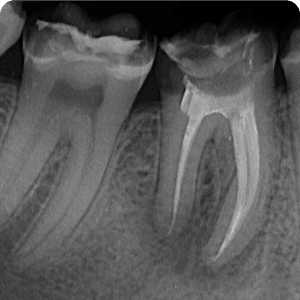

Periapical conditions can also arise when the root canals are not properly filled. In such cases, a root canal re-treatment is performed, which involves refilling the canals. Once correctly filled, these teeth quickly become asymptomatic and remain functional for a long time.